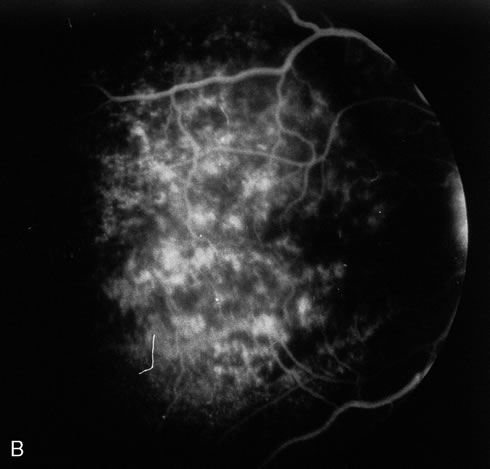

The acute retinal necrosis (ARN) syndrome is most often caused by the herpes zoster virus, although occasionally it may be a result of herpes simplex infection.12 It is typically described in healthy patients although association with immunosuppressed patients has also been described. Granular, nonhemorrhagic areas of retinal necrosis may be observed in the fundus, often rapidly coalescing with resulting blindness often caused by retinal detachment. There is often an associated vasculitis and vitritis. In immunocompromised patients VZV or HSV retinitis may also take the pattern of progressive outer retinal necrosis (PORN) (Fig. 6). PORN differs from ARN in that the former is multifocal, localized to the outer retina, and is less often associated with vasculitis and vitritis.

Pneumocystis carinii pneumonia once was the most common presentation of AIDS. It is typically of insidious onset, with features including dry cough, dyspnea, and a diffuse bilateral interstitial infiltrate evident on a chest roentgenogram. Typical multifocal fundus lesions have been described. They are yellow-white and have a characteristic pattern on fluorescein angiography (Fig. 10A, 10B, and 10C). Diagnosis is made by demonstrating the protozoon via sputum induction, bronchioalveolar lavage, and transbronchial or open-lung biopsies. Treatment modalities include trimethoprim-sulfamethoxazole (TMP-SMX).31